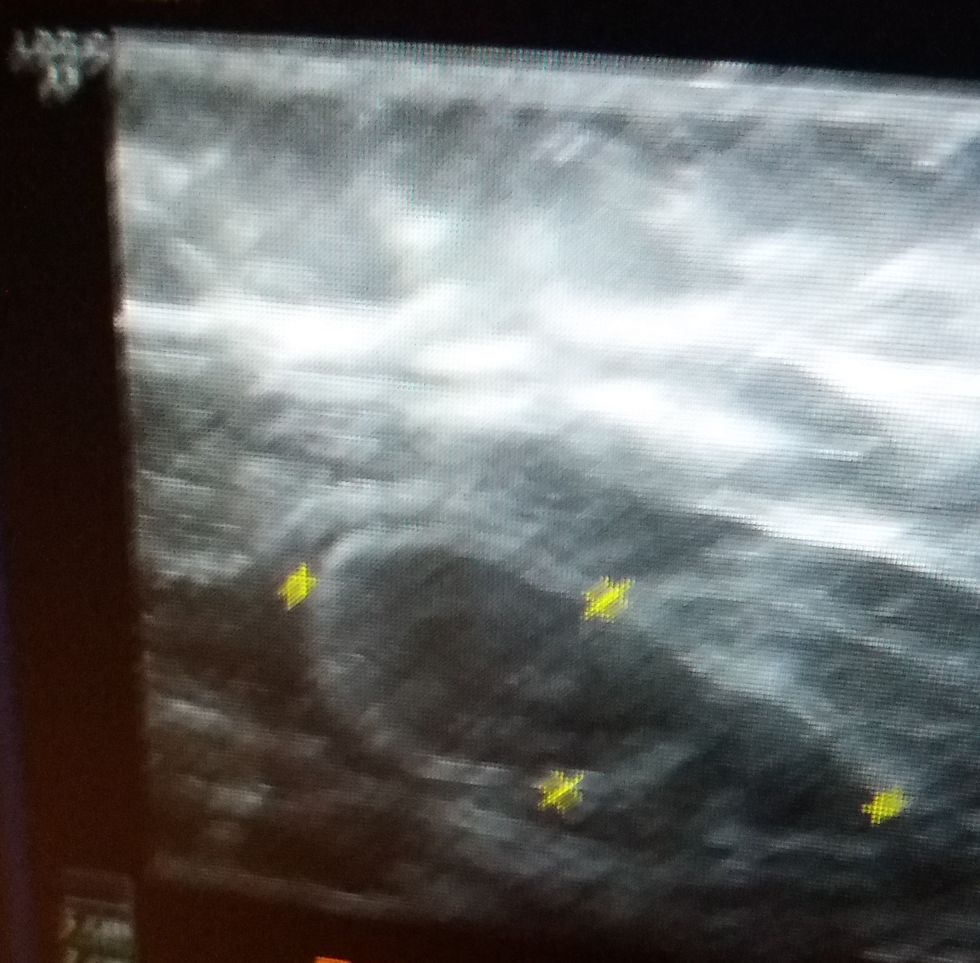

Benign-appearing lymph nodes with a fatty hilum (3cm):

Fatty hilum? Basically that describes the "shell" of this inflammation. If it didn't have that fatty hilum it would be at risk for being a cancerous finding. This is one of the ultrasound findings of my abnormal mammogram this year. Even though this is categorized as benign, the idea that I have a 3 cm fluid-filled lymph node in my right lateral breast is unnerving. Why? Because it doesn't belong there!

Tiny Cyst (4mm):

I also had a tiny cyst found in my right breast on ultrasound, as follow-up for my abnormal mammogram this year. Still benign-appearing, yet you might still find me ducking into a corner now and then at the idea that one of my mammary glands created another fluid-filled sac.